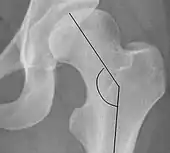

Center-edge angle of Wiberg

The superior-lateral coverage of the femoral head.

• >20° (<55 years old)[notes 2]

• <24° (>55 years old)[notes 2]

• >40° indicates overcoverage